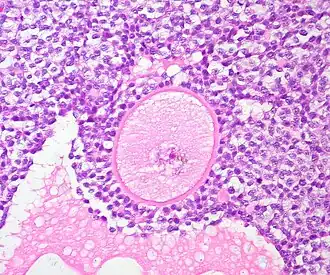

- Culture the cortical ovarian tissue to enhance primordial follicle (immature follicle) growth and isolate the primordial and primary follicles

A common source of ovarian tissue used comes from tissue excised from the patient prior to cancer treatment, which is then cryopreserved.[7] The tissue is then cultured to activate the primordial follicles and allow them to develop.[2] To isolate the follicles, a combination of enzymatic and mechanical tissue digestion has shown to be the most effective method to yield a high quantity of follicles whilst maintaining their quality.[8] The enzymes used, liberase DH and DNase, are produced by good manufacturing practice (GMP) to fully comply with GMP guidelines to ensure future application to patients. The enzymatic digestion process is inactivated every 30 minutes and the suspension is filtered to allow fully isolated follicles to be removed and reduce unnecessary enzyme exposure which may lead to damage of their basement membrane and their death.[8]

When recovering the isolated follicles, malignant cells may be inadvertently retrieved, which poses the risk of re-introducing malignant cells into the patient.[8] To minimise the risk of contamination, the isolated follicles undergo a washing step which involves rinsing the follicles with fresh dissecting media, three times, to separate them from surrounding isolated cells.[2][8]